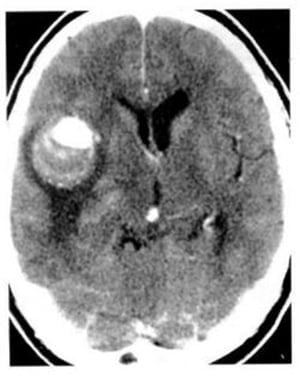

Hình 1.42. Áp xe não mủ. Khối tụ mủ và mô hoại tử có mật độ thấp ở trung tâm không bắt chất cản quang, có vỏ xơ bao bọc bắt chất cản quang. Phù thể tích nhỏ.